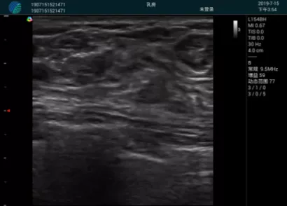

可視化穿刺引導(dǎo)

M20實(shí)時(shí)引導(dǎo):向包塊后方間隙注射利多卡因

清晰顯示腺體內(nèi)低回聲快影,邊界清晰,包膜較光滑

確定進(jìn)針路徑并實(shí)時(shí)監(jiān)測(cè)抽吸針與腫塊位置關(guān)系

抽吸針進(jìn)入腫塊內(nèi)部進(jìn)行旋切

抽吸過程中可見腫塊明顯縮小,并根據(jù)腫塊位置改變針道位置

抽吸旋切后再進(jìn)行超聲復(fù)查,原腫塊區(qū)域未見殘留組織及出血

超聲引導(dǎo)下抽吸旋切取出的腫塊組織